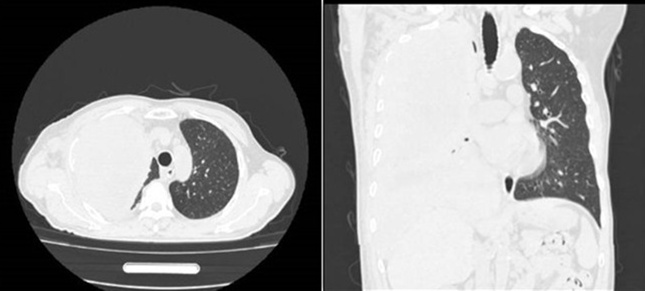

当患者再次回到烟台市烟台山医院时,病情进展已经导致肿瘤占据整个右侧胸腔,并伴随骨及淋巴结转移,严重压迫肺部及周围组织。患者出现明显的喘憋症状,稍作活动便呼吸困难,同时伴随频繁咳嗽、咳痰,生活质量受到严重影响,生命也面临严峻威胁。

患者治疗前巨大肿块,占据右侧整个胸腔。